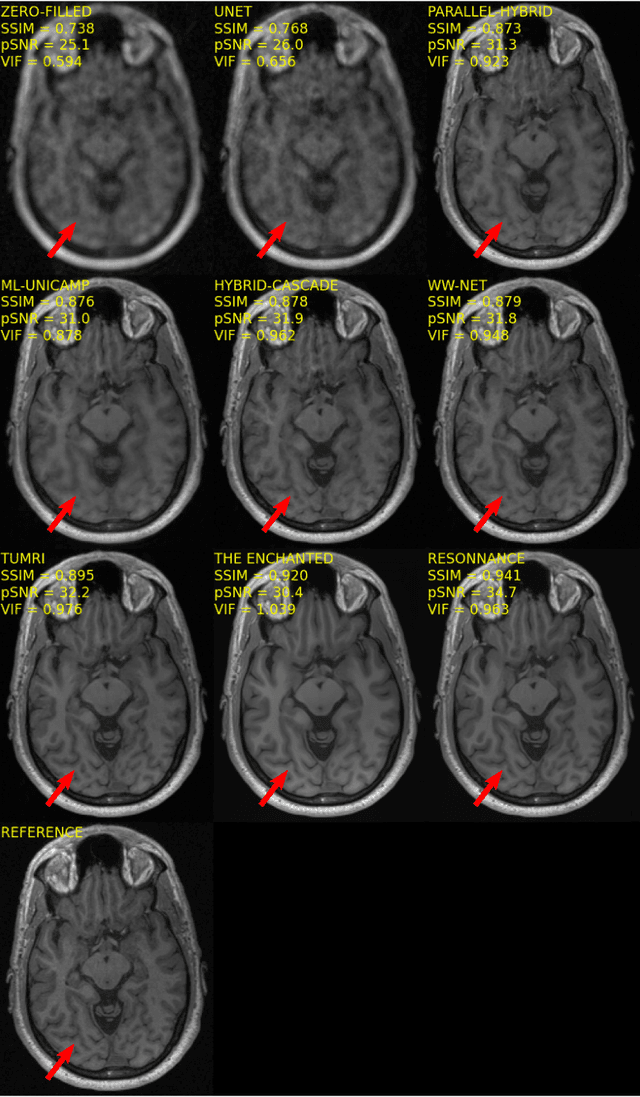

Abstract:The 2020 Multi-channel Magnetic Resonance Reconstruction (MC-MRRec) Challenge had two primary goals: 1) compare different MR image reconstruction models on a large dataset and 2) assess the generalizability of these models to datasets acquired with a different number of receiver coils (i.e., multiple channels). The challenge had two tracks: Track 01 focused on assessing models trained and tested with 12-channel data. Track 02 focused on assessing models trained with 12-channel data and tested on both 12-channel and 32-channel data. While the challenge is ongoing, here we describe the first edition of the challenge and summarise submissions received prior to 5 September 2020. Track 01 had five baseline models and received four independent submissions. Track 02 had two baseline models and received two independent submissions. This manuscript provides relevant comparative information on the current state-of-the-art of MR reconstruction and highlights the challenges of obtaining generalizable models that are required prior to clinical adoption. Both challenge tracks remain open and will provide an objective performance assessment for future submissions. Subsequent editions of the challenge are proposed to investigate new concepts and strategies, such as the integration of potentially available longitudinal information during the MR reconstruction process. An outline of the proposed second edition of the challenge is presented in this manuscript.